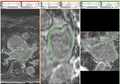

The module can be installed from the extension manage (Figure S1). After that, the module can be found in the Segmentation module category. Its usage is shown in Figure S2. When the computation is done, one of the results is shown in Figure S3.